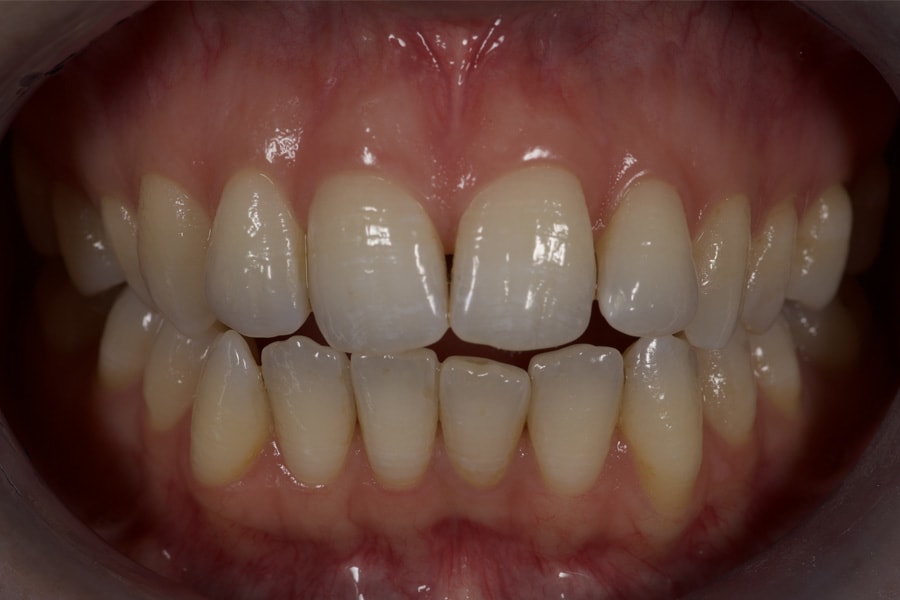

A 31-year-old female patient presented with the following intraoral conditions: an anterior open bite, bimaxillary crowding, negative crown torque, early “black triangles,” and a thin phenotype/biotype with early recessions. Her extraoral situation included a gummy smile with high-lip mobility, asymmetric arch forms and posterior corridors, and incompetent lip closure (Figure 2 through Figure 4). Collectively, these factors increase esthetic and periodontal risk and favor posterior intrusion over anterior intrusion.4-8,12-16